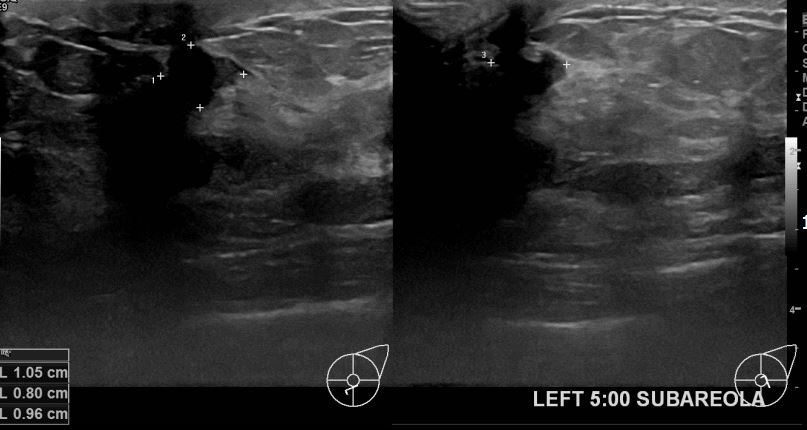

아산유외과 개원후 641번째 유방암진단

상기환자 외부검사상 이상소견으로 내원하신 40대여성으로 좌측 유방의 의심스러혹

조직검사시행해 유방암 진단되었읍니다